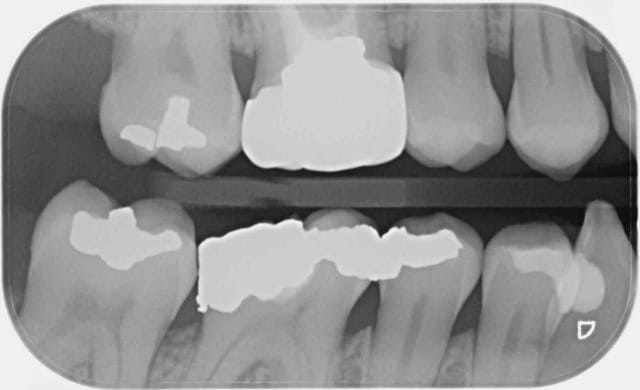

Ce message n'apporte rien au débat, c'est juste pour parler de cette patiente qui n'avait pas donné suite au devis pour couronner la 46. Au contrôle annuel suivant, la dent était couronnée, tout allait bien. Il a fallu que je lui pose la question pour qu'elle m'explique, sans la moindre gêne, que sa mutuelle GROUPAMA l'avait orientée vers un dentiste partenaire "moins cher".

Rien que sur la radio, je vous laisse admirer la qualité de la morphologie occlusale, le profil d'émergence, les points de contact (ou leur absence)... Je n'ai pas osé prendre de photo de ce blockhaus.

Bref, un an après, voici que la patiente revient pour me dire que la couronne ne va pas du tout, que ça la gêne.

On comprends comment il peux s'aligner sur les tarifs du réseaux en éclusant son lot de bagues de cuivres. Par contre, il faut encore trouver un prothésiste du même acabit.